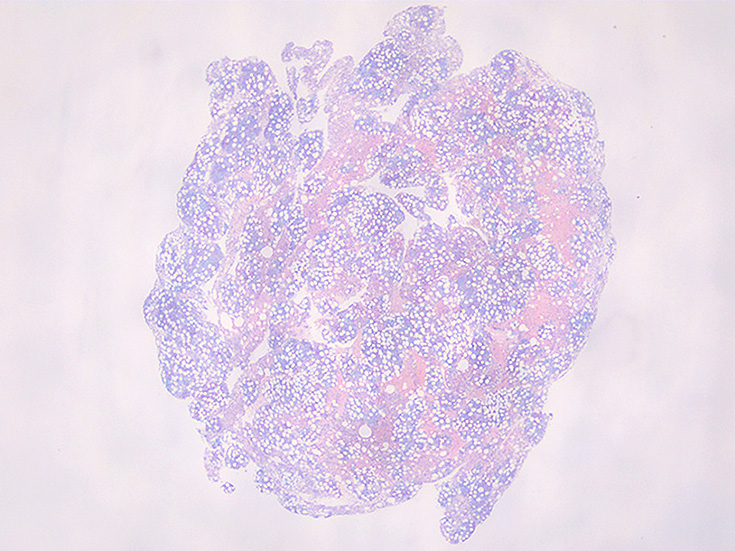

骨髄吸引クロット組織

cellularity 50-60%. 3系統造血細胞の増殖を認める. maturation arrestはない.

特に赤芽球系細胞が強く増殖している所見ではなく, 顆粒球系細胞増多がめだち, 巨核球の増加もある.

ETを含む慢性骨髄増殖性腫瘍 MPNの多くは, 多かれ少なかれ巨核球増多がみられ, CMLでも巨核球増多が見られる症例が多く, PVはより巨核球の増多が見られる.